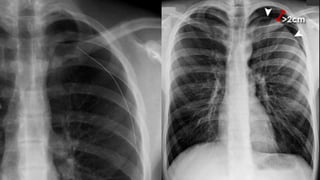

The characteristics of

pneumothorax

◦ Pleural line

◦ No lung markings in

The outer margin of

visceral pleura separated

from the parietal pleura

by a lucent gas space

devoid of pulmonary

vessels

Erect

Small

Apical lucency

Visceral

pleural line

Large

(>2cm in width)

Tension

Lung collapse

Mediastinal shift

Low flat

diaphragm